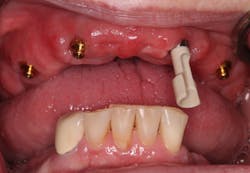

Technique for determining the need for a reline—maxilla:

Since a minimum of four implants are in place, it is very difficult to feel a "squish." Instead, I line the inside of the denture with light-body impression material, seat the denture on the abutments, and remove the denture after the material sets. Probe the impression material in multiple locations (figures 16–18). If probing is shallow and consistent through the denture, a reline is not indicated. If any areas are deeper, a reline is indicated. Note: The attachments are clearly visible in Figures 17 and 18, but often a thin layer of impression material will cover them.